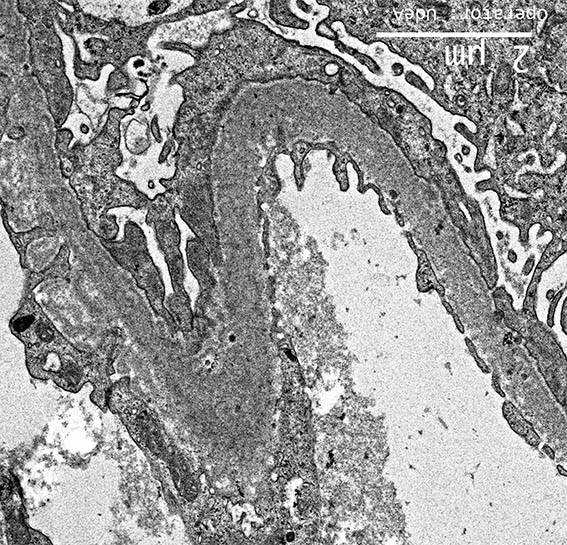

Figure 8. EM, original magnification, X2,500.